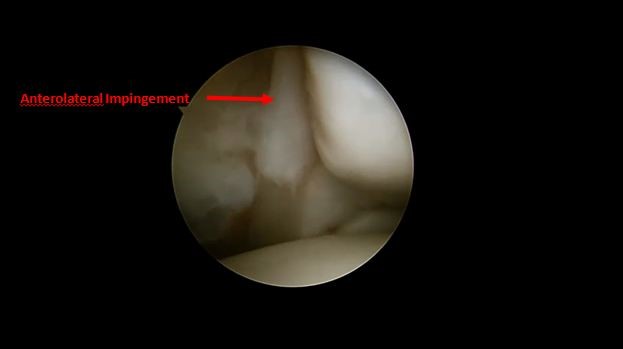

Передний импиджемент голеностопного сустава (голеностопный сустав футболиста)

Импиджемент возникает, когда кость или мягкие ткани на передней части голеностопного сустава воспаляются. Симптомы включают боль и отек голеностопного сустава. Это может ограничить тыльное сгибание в голеностопном суставе. У пациентов при ходьбе в гору часто возникает боль. Остеофиты (костные наросты) в переднем отделе голеностопного сустава можно увидеть на рентгеновском снимке. Артроскопия может использоваться для удаления от воспаленных тканей и костных наростов (остеофитов).